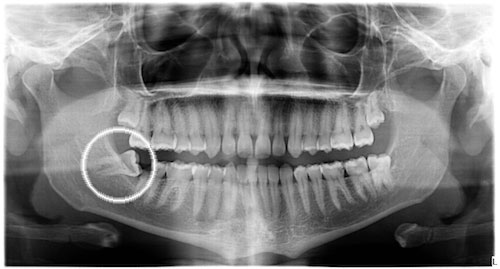

¿Cuándo extraer las muelas del juicio?

Las muelas del juicio, también llamadas terceros molares o cordales, generalmente erupcionan entre los 17 y 26 años. Estos son los últimos dientes en salir, y normalmente erupcionan justo por detrás de las últimas muelas (segundos molares). Al erupcionar los cordales, es normal que se tengan molestias, incluso cuando estos [...]